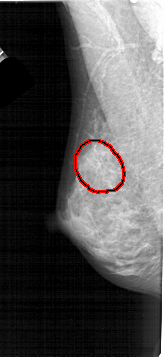

FILE: A_1446_1.LEFT_CC.OVERLAY

TOTAL_ABNORMALITIES 1

ABNORMALITY 1

LESION_TYPE CALCIFICATION TYPE AMORPHOUS DISTRIBUTION SEGMENTAL

ASSESSMENT 2

SUBTLETY 3

PATHOLOGY BENIGN

TOTAL_OUTLINES 1

BOUNDARY